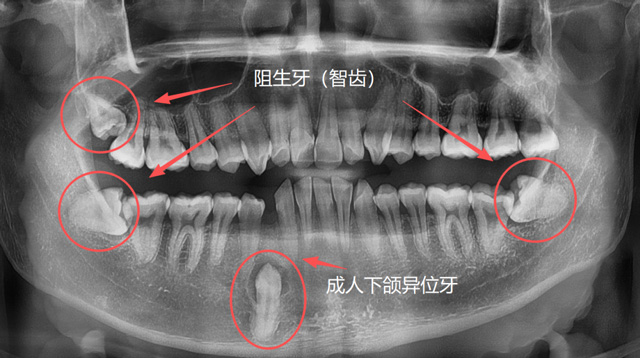

问:什么样的牙比较难拔?

成人异位牙、阻生牙(智齿)

有些人因为牙列拥挤、乳牙滞留或先天发育等原因,恒牙没有在正常的位置萌出,反而往上颌窦、鼻腔等方向生长;称为“异位牙”,还有的牙因为全部或部分埋在了牙槽骨里,无法萌出,称为“阻生牙”,很多智齿就是这样的情况;还有一些超出正常数量的“多生牙”,通常也埋在牙槽骨里无法萌出。